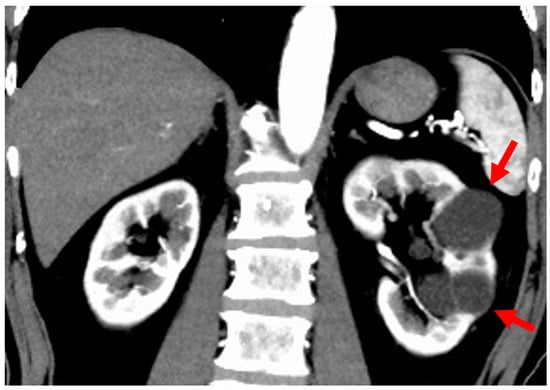

3.1. Autosomal Recessive Polycystic Kidney Disease (ARPKD)